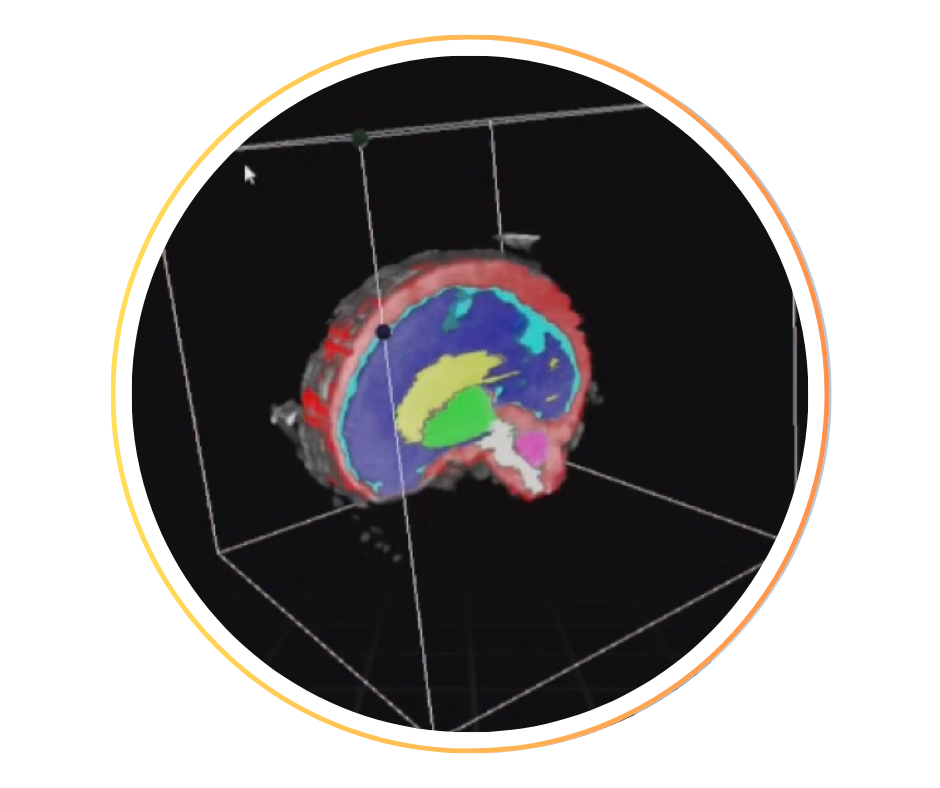

• Cœur fœtal, développement normal et cardiopathies : fusion écho/IRM cardiaque, segmentation, volumétries cardiaques.

• Cerveau fœtal, développement normal et neuro-pathologies : fusion écho/IRM cerveau, perfusion cerveau ASL, tractographie, segmentation, analyse gyration.